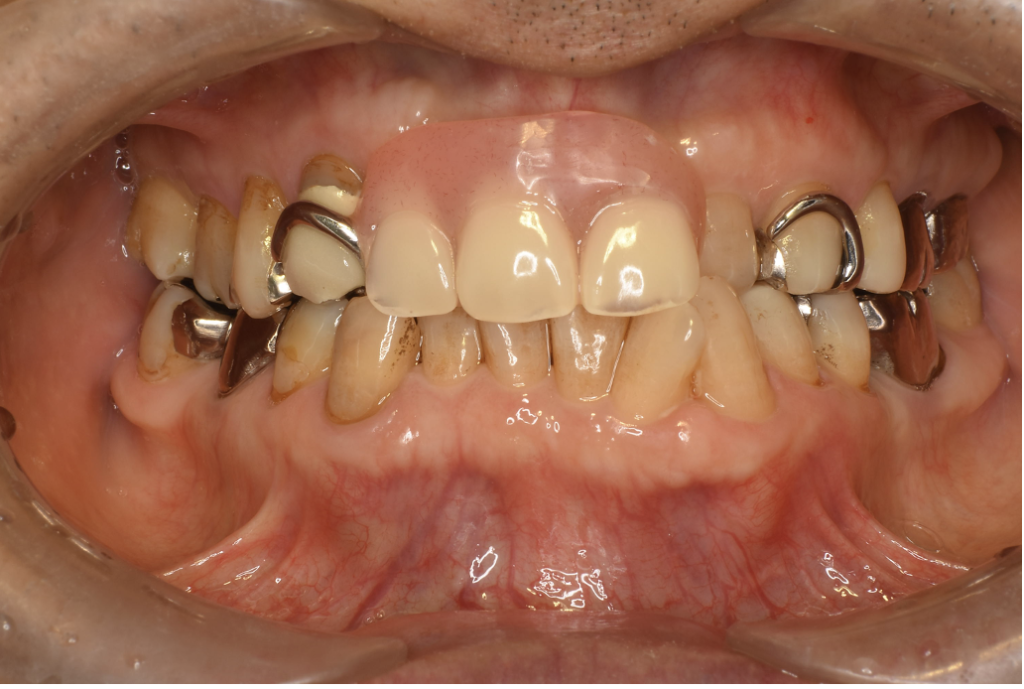

ノンクラスプ+金属床 1 No.13

Before

After

| 治療方法 | ノンクラスプ+金属床 入れ歯に金属のバネがある・ないの違いだけで口元の見た目は大きく変わります。金属のバネがない入れ歯「ノンクラスプデンチャー」は快適で自然な美しさのある入れ歯です。 金属床義歯は土台(床)の部分が金属で薄く作られる入れ歯です。保険の入れ歯に比べて厚みが出ないので、食べ物の温度を感じられ、食事を美味しく取ることができます。素材はコバルトクロムやチタンが使われます。 |

| 費用 | ¥198,000 |

| 通院回数 | 1ヶ月〜3ヶ月 |

| 備考 | 院長より 保険の入れ歯を使用されていたのですが、見た目が気になるのと、違和感が大きいということを悩まれていました。ノンクラスプ入れ歯を使用することで、見た目が自然になり、金属床にすることで違和感が軽減されます。 |